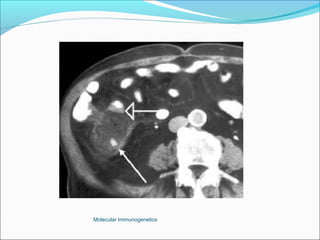

Computer Tomography: More superior to USS in diagnostic accuracy.

The Appendix -Acute Appendicitis Investigations White cell count: high sensitivity 96%, low specificity Urine analysis Plain Xray, nonspecific Ultrasound highly sensitive (80-90%), excludes other pathologies. Computer Tomography: More superior to USS in diagnostic accuracy. Barium enema: Good accuracy, but technically difficult and false positives are common. Laparoscopy Active observation Computer aided diagnosis. Peritoneal lavage Molecular Immunogenetics